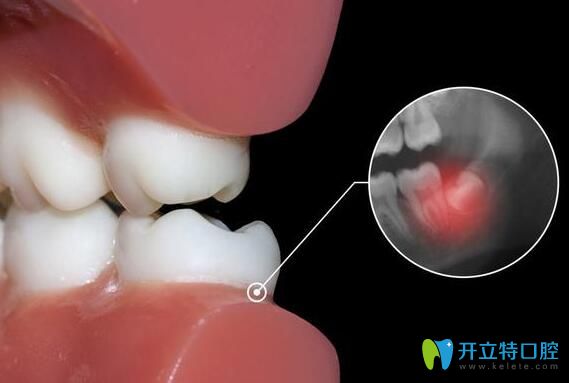

一般長智齒后,人的牙齦部位會出現(xiàn)腫痛、發(fā)炎、有的還會引發(fā)蛀牙等情況,從而影響正常的生活,給身體帶來明顯的影響,這些智齒就需要及時拔掉了。如果,智齒從萌出到后續(xù)生長的過程中,沒有出現(xiàn)任何不良癥狀,也是正常發(fā)育,就不需要拔掉智齒了。具體智齒要不要拔,還得看實際情況而定。

阻生智齒